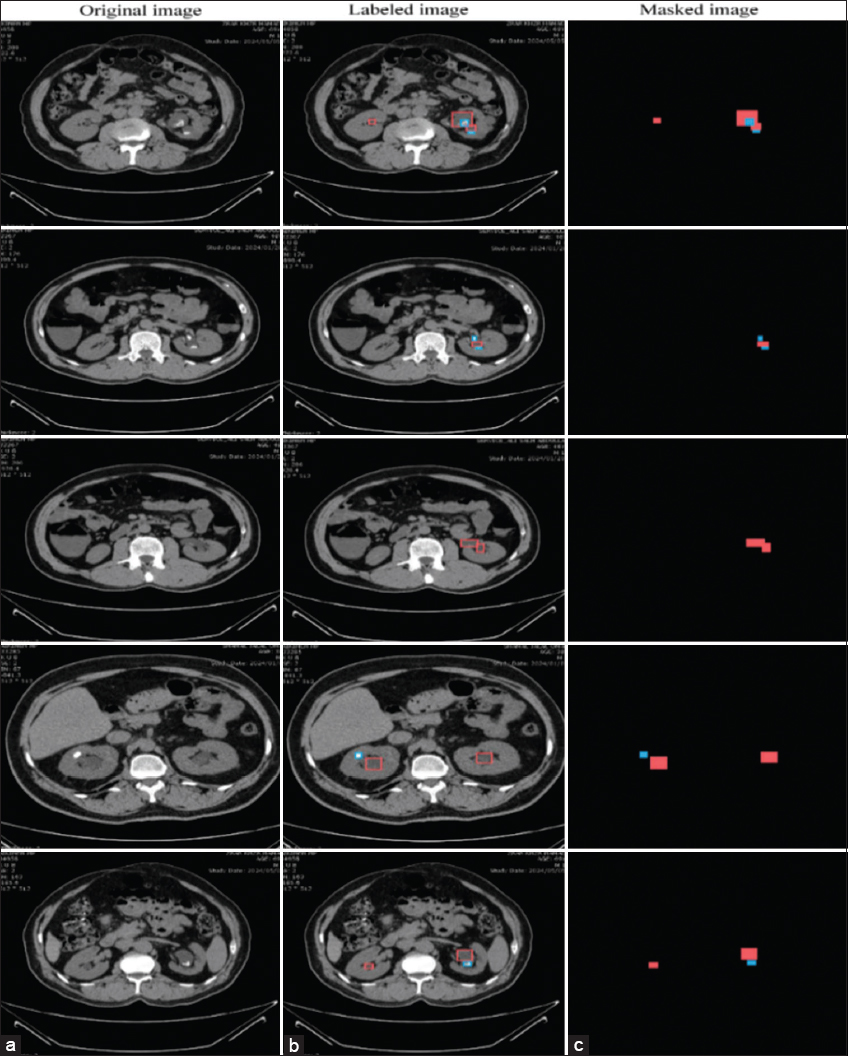

The JSON file serves as the primary reference for producing the appropriate segmentation mask. Automation of this procedure was achieved with Python scripts, which guarantee uniform and accurate extraction of mask regions. Fig. 4 shows an example of this procedure.

thumblarge

Fig. 4. (a) Some original images; (b) labels the images; (c) creates masks from the JSON file; the red color represents kidney disease, and the blue color represents kidney stones.